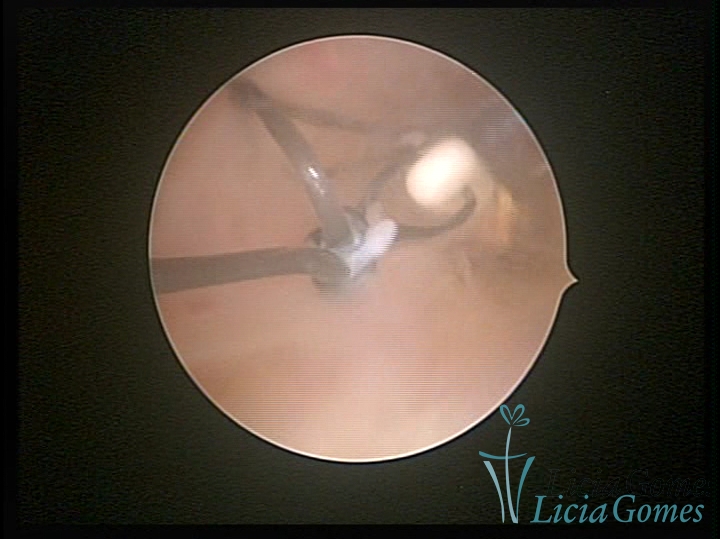

Cavity with Mirena®, being removed under direct view

×